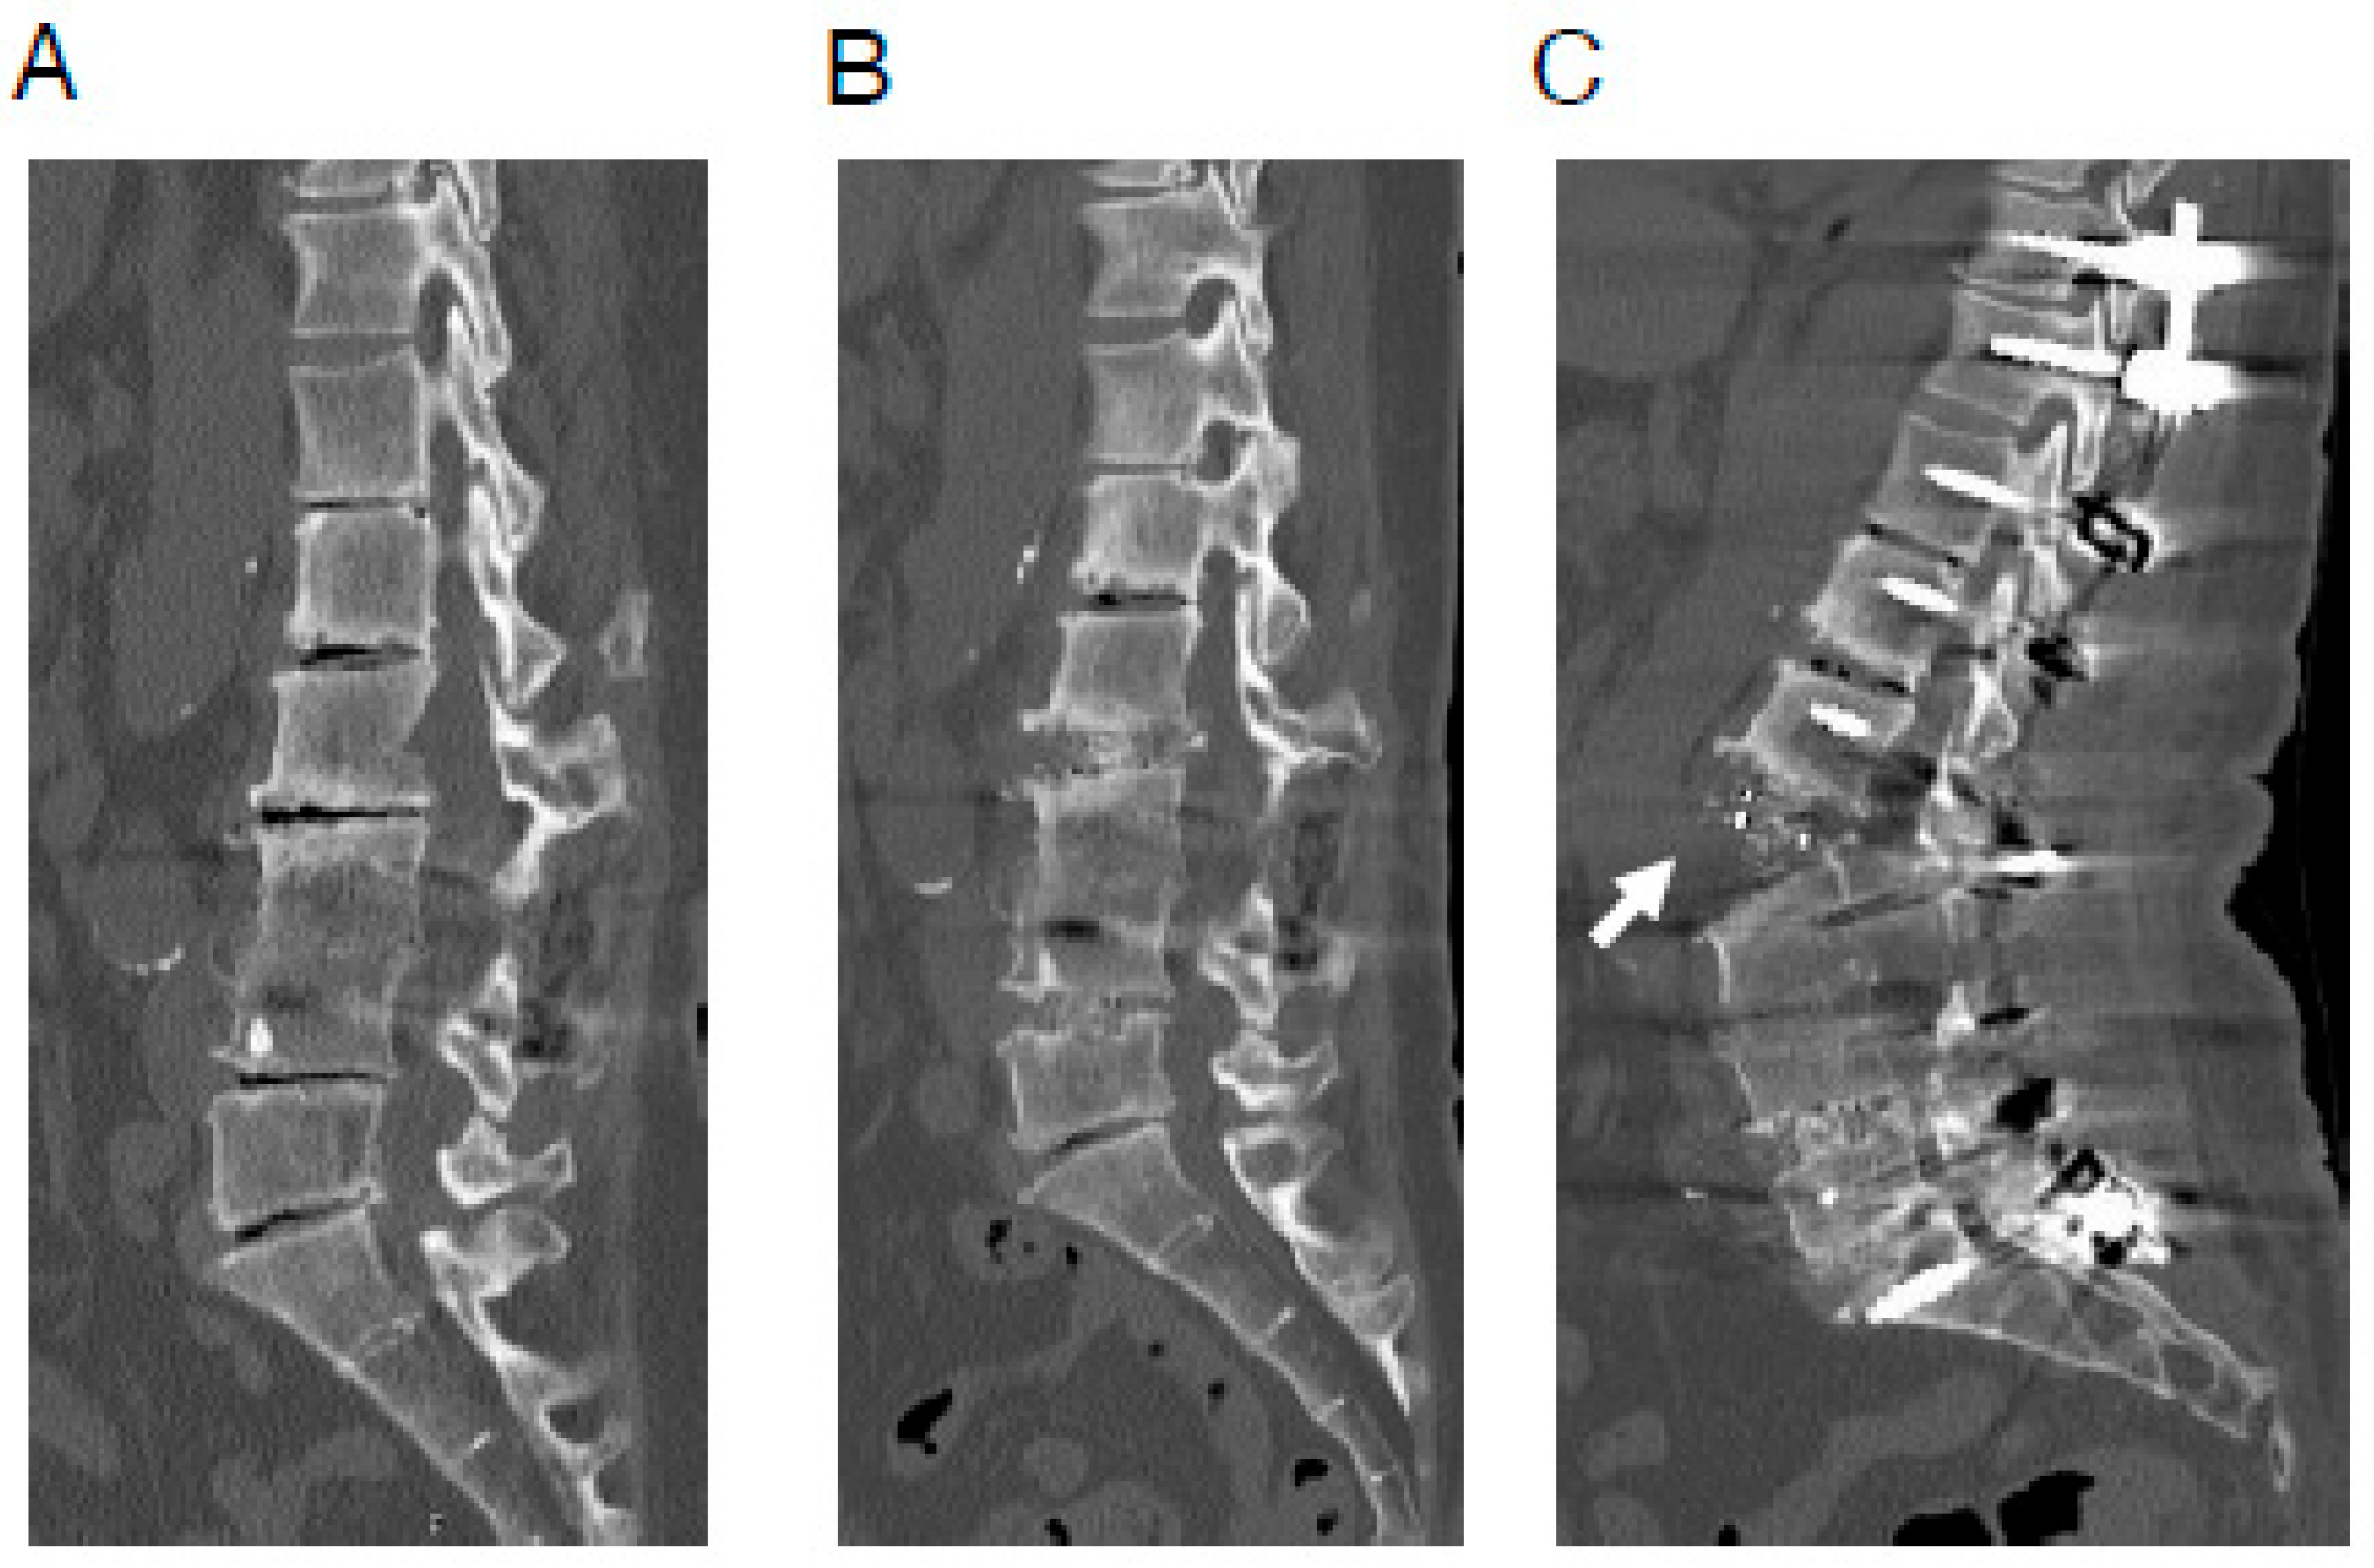

However, we currently have several unresolved issues. One of the notable current issues is the occasional rupture of the anterior longitudinal ligament (ALL) observed during posterior corrective procedures for ASD using LLIF (Figure 1) [14,15,16]. As ALL rupture increases the risk of pseudoarthrosis, preventing it is paramount. However, the exact mechanism of ALL rupture during posterior corrective procedures remains unclear. Finite element analysis (FEA) is a computational method originally developed in industrial sectors, such as construction, and subsequently applied in biomechanical studies in the medical field to simulate mechanical scenarios using computer models [17,18,19,20,21,22,23,24,25,26,27,28,29,30,31]. We have employed FEA to investigate the mechanism of ALL rupture during posterior corrective procedures from various perspectives [32].

As mentioned above, corrective surgery for ASD has made significant progress in various ways [10,11,12,13,14], but several unresolved issues remain. One particularly noteworthy issue is the occasional rupture of the ALL during posterior corrective procedures for ASD (Figure 1). ALL rupture increases the risk of pseudoarthrosis, so its prevention is essentially important [14,15,16]. While using some kind of instrumentation during anterior cage placement may prevent ALL rupture during posterior correction, it is not a desirable option because it makes it impossible to achieve further lumbar lordosis through additional posterior osteotomy. Therefore, it is important to identify the cause of ALL rupture during posterior correction so that preventive measures can be taken. However, the exact mechanism of ALL rupture during posterior corrective surgery remains unclear. ALL rupture during posterior correction is thought to be a multifactorial phenomenon, and we have conducted various analyses to date. We have previously reported that one of the causes is likely to be the use of a cage with an insufficient lordotic angle that is inappropriate for the degree of posterior osteotomy [32].

Figure 1. A representative case of ALL rupture during posterior correction procedure. A 64-year-old woman with adult spinal deformity, who had undergone postero-lateral fusion at the L3/4 level previously at another hospital. (A), Preoperative CT image. (B), CT image after OLIF (L2/3·L4/5). (C), CT image after posterior correction procedure. In this case, surgery was performed using less lordotic (6°) OLIF cages, which were most lordotic cage available at the time. ALL rupture (white arrow) was observed after the posterior correction procedure. ALL indicates anterior longitudinal ligament; CT, computed tomography; OLIF, oblique lateral interbody fusion.